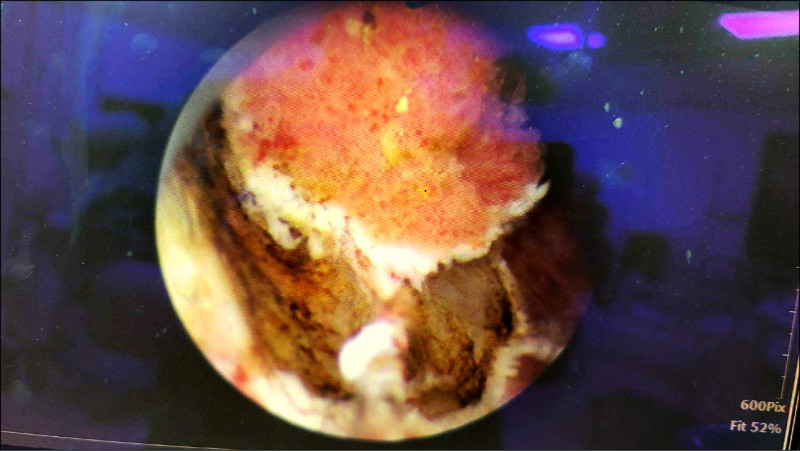

高雄市立民生醫院泌尿科主任蔡秀男指出,臨床常見高齡男性因攝護腺肥大多年,表面佈滿脆弱的靜脈曲張血管叢,一旦血管破裂可能導致大量出血,並在膀胱內形成血塊,未即時處理可能引發尿滯留甚至出血性休克。這名長輩透過超音波檢查發現膀胱嚴重尿滯留約700毫升,導尿後膀胱內仍積存大量鮮血與血塊,情況一度危急。

雷射縮短手術時間 降併發症風險

蔡秀男表示,手術醫療團隊運用先進的「二極體雷射(波長1470nm)」手術系統,藉由其優異的汽化與組織止血特性,精準針對出血點進行凝固,並同步將攝護腺組織切除與刨除。相較傳統電刀手術,雷射手術能有效減少術中出血量,縮短手術與麻醉時間,對於高齡或患有心血管疾病者安全性相對提升,降低併發症風險,亦有助於縮短病患住院天數。